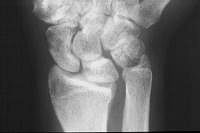

This patient had undergone a radial head excision as primary treatment for his radial head fracture.

Prior radial head excision.